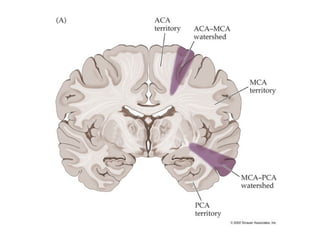

Vascular territories of the brain

Watershed zones